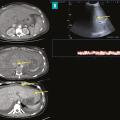

Les atteintes possibles des petits vaisseaux du foie sont au nombre de quatre (fig. 1)  :la maladie vasculaire porto-sinusoïdale (MVPS)  ;le syndrome d’obstruction des sinusoïdes, appelé également «  maladie veino-occlusive  », caractérisé par l’obstruction des sinusoïdes et des veinules hépatiques par des…

Thrombose porte et ischémie mésentérique veineuses